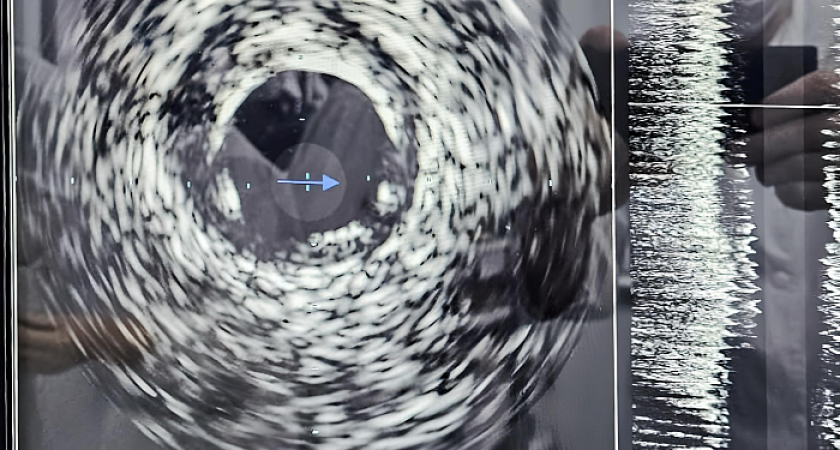

Фото правительства Кировской области О новой уникальной технологии внутрисосудистого ультразвукового исследования, которую теперь используют в Кировской областной клинической больнице  сообщили в  облправительстве.

О новой уникальной технологии внутрисосудистого ультразвукового исследования, которую теперь используют в Кировской областной клинической больнице  сообщили в  облправительстве. Инновация помогает выявить проблему на ранней стадии и обойтись без операций на сердце.

Проводимое с помощью ультразвукового датчика исследование поможет узнать о составе атеросклеротической бляшки, степени сужения артерии и многом другом, рассказал заведующий отделением Евгений Перевалов. Метод позволит предотвратить развитие серьезных заболеваний, но самым главным достоинством инновации является возможность продлевать жизни пациентам, помогая избежать открытого хирургического вмешательства.